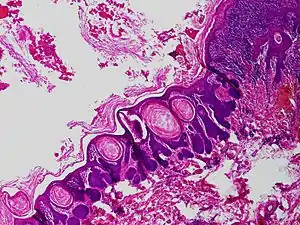

Trichofolliculoma

Trichofolliculoma is a cutaneous condition characterized by a benign, highly structured tumor of the pilosebaceous unit.[1]: 671 [2]